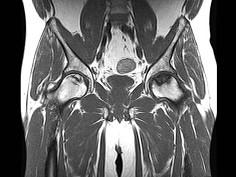

问题 男,47岁,长期左髋痛,请结合CR和MRI片,选择最可能的诊断 ( )

选项 A、暂时性骨质疏松 B、股骨头缺血坏死 C、退变性囊肿 D、骨岛 E、髋关节结核

答案 B